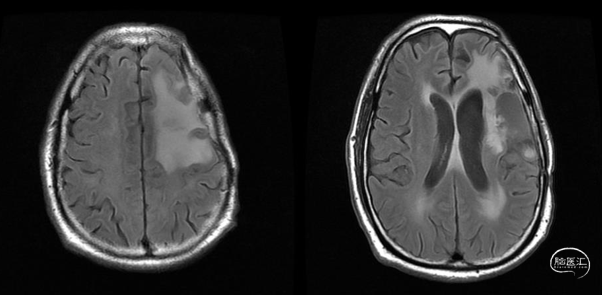

放疗后17月(2021-12-20)MRS显示左颞叶感兴趣区Cho/NAA约1.19-5.53:图示。

放疗后17月(2021-12-20)PWI显示感兴趣区脑血容量及血流量较对侧高低不一,平均通过时间及达峰时间延长,提示左侧病变区血流灌注降低:图示。

术后5周开始实施标准的新STUPP方案的辅助治疗,即在同步放化疗后,辅助替莫唑胺化疗的同时使用了电场治疗。目前生存25月,且临床和影像学表现均提示稳定,未见复发迹象。期间,在放疗后7月时复查MRI提示异常FLAIR信号区增大,经我院MDT讨论,考虑到强化信号减轻,无明显占位效应,患者无症状体征,考虑是治疗后水肿,非进展,故继续按原方案治疗。放疗后17月复查MRI出现术区边缘局部强化范围稍增大,但PWI示强化区局部呈低灌注且未见弥散受限表现,MDT讨论考虑为假性进展,继续原方案治疗。后续复查MRI强化范围减轻,证实了MDT的判断证实疾病稳定。患者生存时间已达25个月。全程安全顺利,仅出现一过性轻度皮肤反应。

辅助TMZ治疗过程中每2-3月复查MRI。治疗中曾出现水肿范围增大,尽管有部分区域弥散受限和MRS异常及血流量增加,但是临床症状未加重,仍继续原方案治疗,后续监测PWI显示病变区灌注减低。提示持续肿瘤电场治疗可以使病变长期稳定。此患者每天佩戴肿瘤电场治疗时间接近22小时,中间出现头皮发红和小水泡,经局部外用皮质类固醇和外用抗生素,暂停2天治疗恢复。至今随访25月稳定。说明肿瘤电场治疗联合TMZ治疗较单TMZ治疗明显延长胶质母细胞瘤患者PFS及OS,临床应积极推广使用。